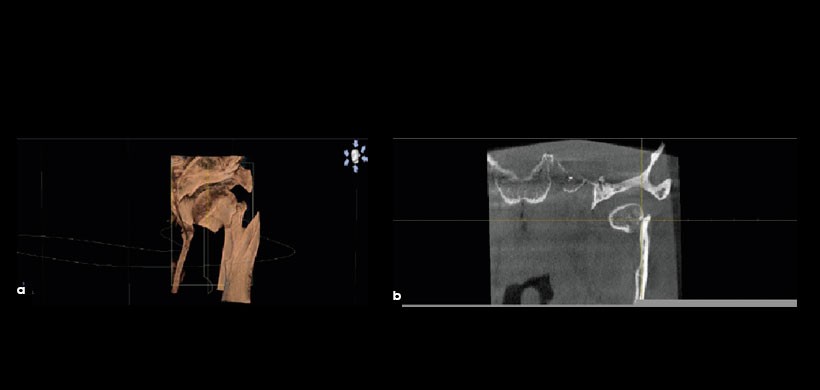

Fig 2. (A) Vista tridimensional de la cabeza fracturada de un cóndilo. La imagen también muestra la cavidad glenoidea, apófisis estiloides, y la cara interna de la rama mandibular. (B) Vista transversal de la cabeza del cóndilo fracturado